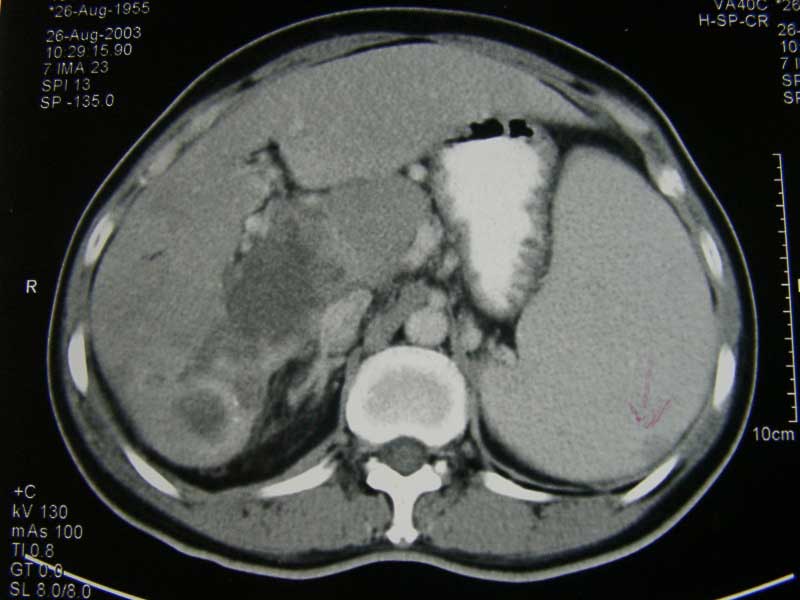

Seam (B984), seoarang wanita berusia 49 tahun, didiagnosa hepatoseluler karsinoma pada Agustus 2003. Hasil CT-abdomen pada 26 Agustus 2003 mengindikasikan:

1.   Massa pada segmen 6 dan 7 liver sebesar 8,7 x 6,6 x 10 cm.

2.   Ruptur pada lobus caudatus.

3.   Nodul-nodul peritoneal.

4.   Trombosis vena porta.

5.   Splenomegali (pembesaran limpa).

6.   Dan kemungkinan metastase ke limpa.